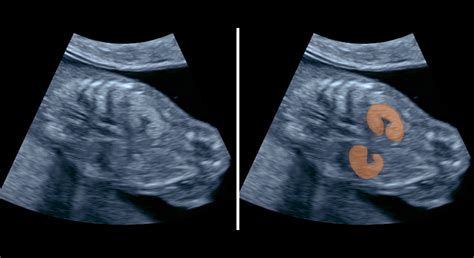

V prvom trimestri sa ultrazvuk používa na stanovenie presného gestačného veku, určenie počtu plodov, vyšetrenie maternice a diagnostiku potratu alebo mimomaternicového tehotenstva.